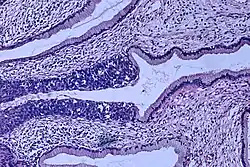

Neoplasia intraepitelial cervical, uma lesão com potencial precursor do câncer do colo do útero, é diagnosticada com frequência na biópsia do colo, examinada por um patologista. A nomenclatura neoplasia intraepitelial cervical é utilizada para alterações displásicas pré-malignas.

O nome e a classificação histológica das lesões precursoras do carcinoma do colo do útero foram muito modificadas ao longo do século XX. A classificação da Organização Mundial da Saúde[36][37] era baseada na descrição das lesões, classificando-as em displasia leve, moderada e grave ou carcinoma in situ (CIS). O termo neoplasia intraepitelial cervical (NIC) foi desenvolvido para enfatizar a gama de anormalidades dessas lesões e para ajudar a padronizar o tratamento.[37] Classifica-se a displasia leve como NIC I, displasia moderada como NIC II e displasia grave e carcinoma in situ como NIC III. Mais recentemente, NIC II e NIC III foram combinadas em NIC II/III. Estes são os resultados que devem ser relatados pelo patologista que analisar a biópsia.

Este sistema não deve ser confundido com o Bethesda que serve para os resultados do exame citológico. As classificações do sistema Bethesda são: lesão intraepitelial escamosa de baixo grau (LSIL), lesão intraepitelial escamosa de alto grau (HSIL) e outras. Um resultado LSIL deve corresponder a um NIC I e um HSIL a um NIC II ou III,[37] porém, trata-se de resultados de exames diferentes e os achados do exame citológico podem não corresponder aos da análise histológica.